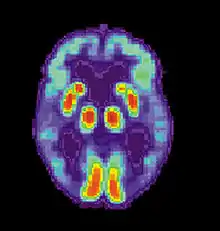

Alzheimer's disease is characterised by loss of neurons and synapses in the cerebral cortex and certain subcortical regions. This loss results in gross atrophy of the affected regions, including degeneration in the temporal lobe and parietal lobe, and parts of the frontal cortex and cingulate gyrus.[84] Degeneration is also present in brainstem nuclei particularly the locus coeruleus in the pons.[85] Studies using MRI and PET have documented reductions in the size of specific brain regions in people with Alzheimer's disease as they progressed from mild cognitive impairment to Alzheimer's disease, and in comparison with similar images from healthy older adults.[86][87]

AD is usually clinically diagnosed based on the person's medical history, history from relatives, and behavioral observations. The presence of characteristic neurological and neuropsychological features and the absence of alternative conditions supports the diagnosis.[114][115] Advanced medical imaging with computed tomography (CT) or magnetic resonance imaging (MRI), and with single-photon emission computed tomography (SPECT) or positron emission tomography (PET), can be used to help exclude other cerebral pathology or subtypes of dementia.[116] Moreover, it may predict conversion from prodromal stages (mild cognitive impairment) to Alzheimer's disease.[117] FDA-approved radiopharmaceutical diagnostic agents used in PET for Alzheimer's disease are florbetapir (2012), flutemetamol (2013), florbetaben (2014), and flortaucipir (2020).[118] Because many insurance companies in the United States do not cover this procedure, its use in clinical practice is largely limited to clinical trials as of 2018.[119]